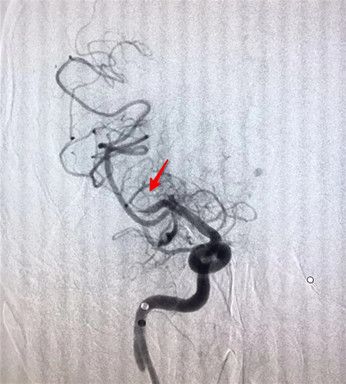

展会主任、张西安副主任医师及豆涛涛医师为患者行局麻下全脑血管造影术。术中见右侧颈内动脉支架远端及颅内段血管完全闭塞。右侧大脑半球通过左侧前交通动脉及右侧大脑前动脉有少量代偿。随后在全麻下,行颈内动脉球囊扩张,造影又发现大脑中动脉M1段也有闭塞、血流仍不通畅。这属于典型的串联病变,治疗难度大。神经外科医生没有犹豫,再行大脑中动脉内支架取栓术。经三次取栓后大脑中动脉完全通畅。术后给予少量的抗血小板治疗。经过4个多小时的手术,李师傅闭塞的血管终于开通了,脑组织恢复了血供,腹腔引流未见明显渗血,目前李师傅病情平稳,在进一步的恢复之中。